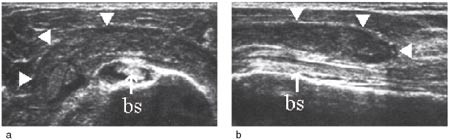

Undersøkelsesgangen er standardisert. Den utføres med pasienten sittende på en roterbar krakk og undersøkeren stående bak. Vi har fem hovedprojeksjoner som fremstiller senene i transversalt og longitudinalt plan og som suppleres med dynamisk undersøkelse. Først utføres to ventrale projeksjoner med armen addusert, og med underarmen supinert, liggende på låret (musculus subscapularis, den lange bicepssenen) (fig 2a, b, e-fig 3a, b). Deretter følger to laterale projeksjoner med addusert og innoverrotert arm, og med underarmen bak ryggen (musculus supraspinatus og infraspinatus) (fig 4 a – c og 5a, b). Til slutt utføres den bakre projeksjonen med armen i utgangsposisjon (e-fig 6a, b). Resultatet dokumenteres på laserskriver eller lagres på diskett. Figurene 2 til 6 viser typiske normale funn.

Vurdering av den lange bicepssenen med ultralyd er mer krevende enn vurderingen av rotatorcuffen. Dette skyldes stor interindividuell variabilitet og hyppige artefakter. Sammenlikning og kontroll av funnene med den kontralaterale siden er derfor påkrevd (8). Typiske funn ved tenosynovitt er enten hyper- eller hypotrofi av senen sammenliknet med motsatt side, redusert ekkogenisitet, ekkofattig halo rundt senen og hvelving av sulcustaket over rotatorcuffnivå (e-fig 11) (3, 9).

Figurene 2b, 3b, 4c, 5b, 6b, 8a og b er tatt med et Siemens Sonoline Antares ultralydapparat med 11,4 MHz lydhode, figurene 2b og 5b i tillegg med teknikk for utvidet bildefelt (extended field of view). Resten av ultralydbildene er tatt med et Siemens Sonoline Sienna ultralydapparat med 7,5 MHz lydhode. Figurene 1a, 1b, 2a, 3a, 4b, 5a og 6a er gjengitt med tillatelse fra Primal Pictures Ltd (). e-fig 3, e-fig 6, e-fig 11, e-fig 12 og e-fig 13 finnes i artikkelen på www.tidsskriftet.no